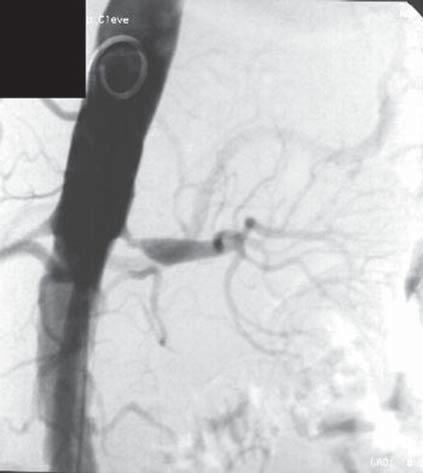

B Wegener)

Question 14 – QCM A

B chirurgie aortique C D

E traitement anticoagulant